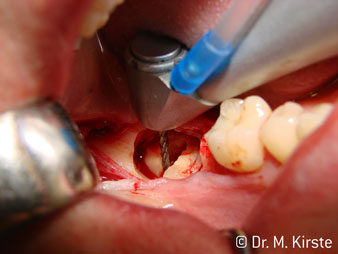

45° açılı angldruva geniş avantaj yelpazesi sebebiyle özellikle seçildi. Bu enstrümanın geliştirilme nedeni olan cerrah meslektaşlarım angldruvaların kısıtlı alanlardaki çalışma yeteneğini yakında takdir edeceklerdir. Özellikle gömük diş çekimlerinde (res. 2) yumuşak dokunun yanak bölgesine doğru yarılmasına gerek kalmaz(res. 3). Angldruvanın kafa dizaynı sayesinde retromolar bölgede hızlı ve güvenli çalışma sağlar.

Hızlı çalışmadan bahsetmişken: angldruva, 100,000 rpm üzerinde çalışırken aynı anda profesyonel bir soğutma sağlanır

Angldruva kafası içindeki profesyonel tasarımlı dişliler frezin sessiz çalışmasını garanti eder; kök separasyonu yapılırken atravmatik operasyona olanak verir. (res. 4-9).

45° açılı angldruva çok rahat kavranıyor. Angldruva çalışırken işaret parmağınızın açısını takit ettiğini görebilirsiniz, planladığınız işlemi kusursuz bir şekilde tamamlarsınız. (res. 1)”